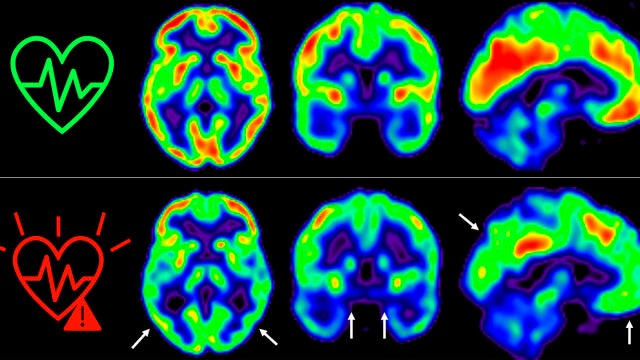

Consumo de glucosa en el cerebro de individuos según su riesgo cardiovascularSinc

El estudio PESA-CNIC-Santander

En 2021, los investigadores del CNIC descubrieron que la presencia de factores de riesgo cardiovascular y de aterosclerosis subclínica -antes de que aparezcan los síntomas- en las arterias carótidas, que son las que suministran sangre al cerebro, en individuos de 50 años aparentemente sanos que participan en el estudio PESA-CNIC-Santander, estaba asociada a un menor metabolismo de glucosa cerebral. El metabolismo de la glucosa cerebral está considerado un indicador de salud cerebral.

El equipo de Fuster, liderado por Marta Cortés Canteli y Juan Domingo Gispert, han seguido a estos individuos a lo largo de 5 años y han encontrado que aquellos que mantienen un riesgo cardiovascular elevado durante todo este tiempo sufren una disminución aún mayor del metabolismo cerebral medido a través de técnicas de imagen como tomografía por emisión de positrones (PET).

"Hemos detectado un declive metabólico cerebral tres veces mayor que el de personas que se mantienen en bajo riesgo cardiovascular", señala Catarina Tristão-Pereira, primera firmante del nuevo artículo y becaria INPhINIT de la Fundación "la Caixa".

Además, el equipo del CNIC descubrió que la progresión de la aterosclerosis subclínica en las carótidas durante estos 5 años se relacionaba con una disminución del metabolismo en regiones cerebrales vulnerables a la enfermedad de Alzheimer, de manera aditiva al efecto de los propios factores de riesgo cardiovascular.